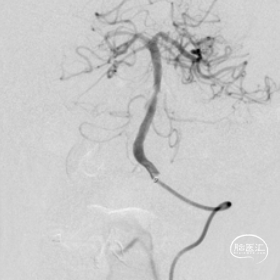

抽吸再通后造影,近端残余明显狭窄且局部毛糙,拟支架成型。

3.0*8 mm球扩支架,小压力,减少穿支损伤。

支架后造影

最后造影